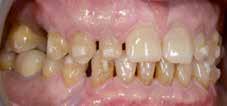

A felnőtt páciensek kezelése során általában egyszerre több ellátásra szoruló elváltozást is diagnosztizálhatunk: hiányzó fogak, kopott fogazat, esetleg régi, nem megfelelő, sérült fogpótlások, rendellenes helyzetben lévő fogak stb… Ezen páciensek kezelésekkel kapcsolatos kérései mindig az esztétikai vagy a rágással kapcsolatos kívánságaik kielégítését szolgálja. A kezelések során a fogorvosoknak nem csak a páciensek kéréseinek teljesítésére, hanem ezzel egyidejűleg a fogazat általános megjelenésének és funkciójának lehetőség szerinti javítására is törekedniük kell. Mindemellett a lehető legtöbb saját foganyag megőrzését és az évek során elvesztett kemény- és lágyrészek pótlását (pl.: hiányzó fogak, sorvadt állcsontgerinc, lágyszöveti defektusok) is szem előtt kell tartaniuk, úgy, hogy közben egy hosszú távon fenntartható eredményekkel járó kezelési tervet állítanak össze. Ezek mindig összetett esetek. Annak érdekében, hogy a fentiekben megfogalmazott összes kezelési célt teljesíteni tudjuk, interdiszciplináris megközelítésre van szükség. Az ilyen komplex rehabilitációs kezeléseket „fogászati megfiatalításnak” nevezzük. Ezeknek a beavatkozásoknak lényege az elhasználódott fogazat biológiai szempontokat figyelembe vevő minimál invazív módon történő helyreállításában rejlik, mely folyamat végére a páciensek fogai visszanyerhetik fiatalkori megjelenésüket.

A rehabilitációs kezeléseknek a célja, hogy a páciensek a lehető leghosszabb időn keresztül képesek legyenek mosolyogni és rágni. A protetikai kezeléseket végző fogorvosoknak helyre kell tudni állítaniuk a fogívek szabályos lefutását és az alsó és felső fogív között megfelelő interokkluzális érintkezéseket kell létrehozniuk. Így lehet csak az ellátás befejezését követően elért végeredmény biológiai szempontokat figyelembe vevő esztétikáját, funkcionális megfelelőségét, hosszú távú fenntarthatóságát biztosítani.